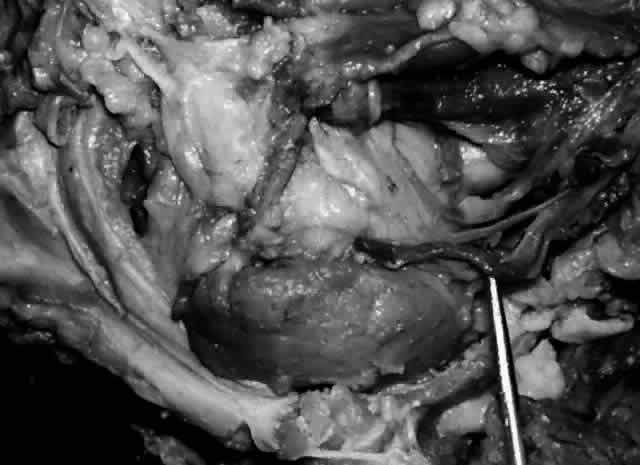

Fig. 7. Secretory ducts (arrow 1) of the right lacrimal gland (arrow 2) are seen passing to the palpebral conjunctiva (arrow 3). (Courtesy of James Sanderson, MD, Orkan Stasior, MD, and George Stasior, MD)

Sanderson and Stasior4 found islands of “peripheral” lacrimal glandular tissue below the lateral canthus unassociated with the main gland in 60% of cadaver specimens (Fig. 8). These peripheral islands of glandular tissue were found less commonly in or above the lateral canthal tendon.

Fig. 8. “Peripheral” lacrimal gland lobules (arrow 1) are seen below the right lateral canthus (arrow 2) and separate from the palpebral lobe of the lacrimal gland (arrow 3). (Courtesy of James Sanderson, MD, Orkan Stasior, MD, and George Stasior, MD)